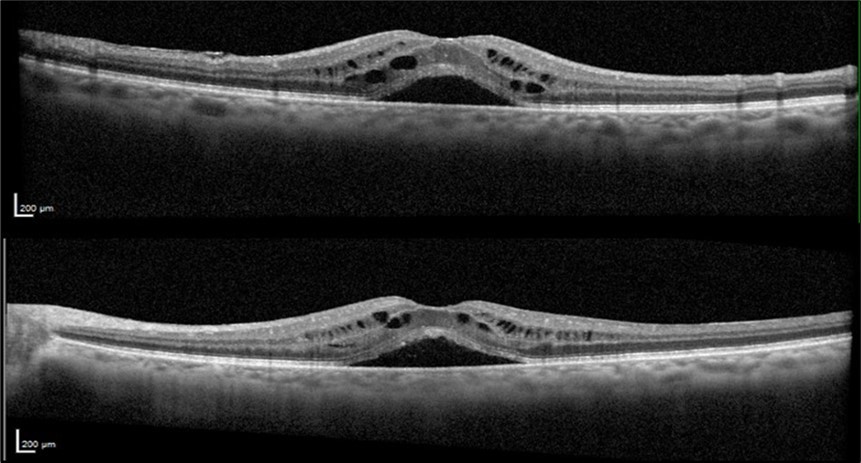

A 75-year-old female with underlying dyslipidemia and rheumatoid arthritis presented to the emergency department with a history of CME and reduced VA in both eyes (OU) for several months. She had undergone cataract surgery 20 years earlier in a different hospital and was currently using topical nepafenac, dorzolamide, and dexamethasone prescribed abroad. Initial VA in the right eye (OD) was 20/50 and in the left eye (OS) was 20/40. Fundus examination was notable for macular edema in OU. OCT OU revealed subretinal foveal fluid and intraretinal cysts (Figure 1).

Figure 1.Optical coherence tomography of both eyes revealing subretinal foveal fluid and intraretinal cysts at the patient's initial presentation to our clinic.